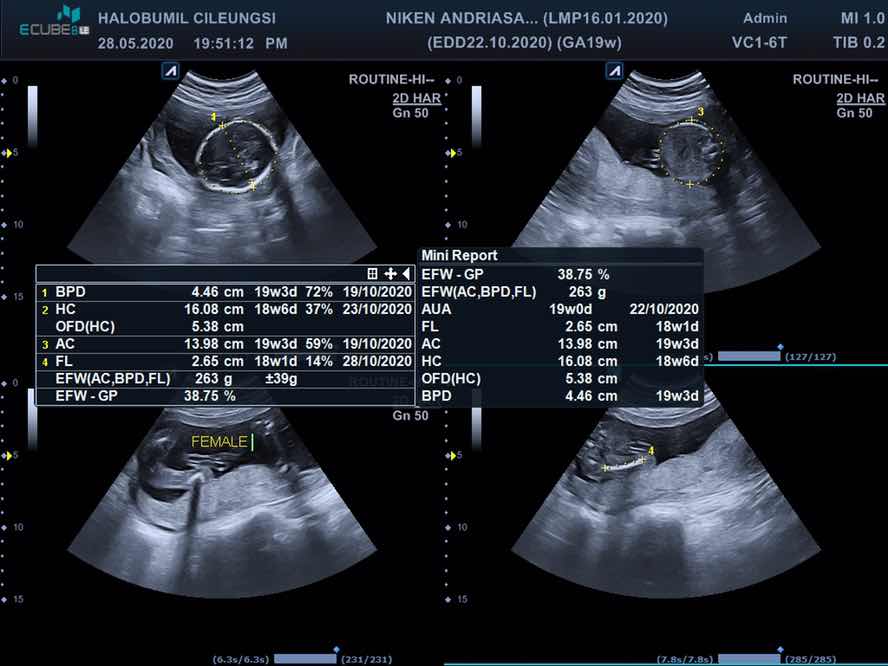

Usg 2d dan 4d

Assalamu’alaikum Selamat pagi bunda Bunda dan ayah manggil aku selama di perut dgn sebutan dede El, aku sekarang 19 minggu Lihat deh poseku kata dokter pas mau di screen shoot tangannya di taro di dagu gini dan anteng bgt padahal sebelumnya petakilan banget (tau aja mau di foto) ?? Berdo’a yuk semoga bunda, dede dan semua bumil yg lg mengandung di beri kesehatan dan kelancaran selalu, Aamiin ??